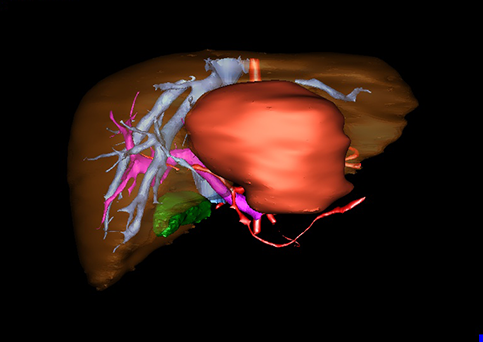

目前常用的检查方法有B超检查、CT、MRI、血管造影等。与其它的腹部肿块的诊断不同,对于小儿肝母细胞瘤血管造影具有重要的意义,可以作为手术前介入治疗的手段,也可为手术提供非常有效的影像学指导,但技术要求高,操作较复杂,且给患儿带来一定的痛苦。近年借助计算机辅助手术系统进行CT原始影像三维重建、手术规划和计算机虚拟手术技术,为精准肝脏手术提供了极为有效的技术支持。

近年来由于数字医学的发展,基于可视化三维重建技术的计算机辅助手术系统极大推进了小儿肝脏肿瘤的精准手术的进步。可以立体透视肝脏解剖、精确掌握肝段的边界、精确测算肝段乃至任意血管所支配的功能体积、准确定位病灶及其与邻近血管的解剖关系,最终对不同手术方案进行比较、筛选和优化。因此,计算机辅助手术规划系统是实现精准肝切除的有力辅助工具,是未来数字外科、精准外科等21世纪外科新理念的重要技术支撑。

计算机辅助手术规划系统具有良好的操作可行性、计算准确性和三维显示效果,可半透明、交互式显示真实的肝内立体解剖关系和空间管道变异,准确计算肝内管道的直径、走行角度,两点间的垂直距离,和任意血管的支配或引流范围等传统二维影像无法获取的信息,有助于实施个体化手术,提高了手术的确定性、预见性和可控性。计算机辅助手术规划系统可直观显示预留肝脏的结构和功能,并可通过虚拟切割功能辅助术者对手术方案进行蹄选和优化,系统评估手术风险和制定对策,改变了部分二维规划的术式和切除范围,使部分二维规划认为不能切除的患者成功手术,提高了手术的根治性、安全性和病变的可切除性,更加符合精准肝脏外科的术前规划要求。详见第11章。

随着计算机技术及影像检查技术的不断发展,以精确的术前影像学和功能评估、精细的手术操作为核心的精准肝切除技术日益受到重视。基于数字医学的计算机辅助手术技术(computer-assisted surgery,CAS)则是实现肝脏精准手术操作的基础。计算机辅助手术系统(CAS)可将术前二维(two dimensional,2D)的CT/MRI影像数据进行三维(three dimensional,3D)重建,建立个体化的肝脏三维解剖模型,清晰显示肝脏内脉管系统的走行及解剖关系,还原病灶与其周围脉管结构的立体解剖构象,准确地对病变进行定位、定性和评估,制定合理、定量的手术方案,实施个体化的肝脏血管取舍分配方案及实施精准肝脏手术。一般认为CAS包括:创建虚拟的患者的图像;患者图像的分析与深度处理;诊断、手术前规划、手术步骤的模拟;术中实时导航。应用本技术后,由于可以更清晰地看出肿瘤的界限,特别是根据肝血管的显影,判断出肿瘤与门静脉及肝静脉的关系以在手术前较准确地估计出手术成功切除的可行性。以往部分根据普通强化CT判断无法手术的病例而被评估为可以成功切除并手术成功。